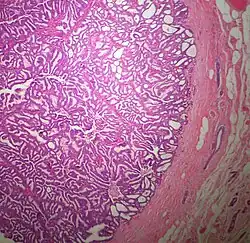

Pathology

The microscopic histopathology (refer to adjacent high-power photomicrograph) of EPC tissues typically shows papillary structures with fibrovascular cores and proliferating neoplastic epithelial cells growing within cystic spaces, all of which are enclosed within a dense fibrous capsule. In general, EPC tumors do not have areas of neuroendocrine degeneration or myoepithelial cells.[6] The presence of a dense fibrous capsule distinguishes EPC from other papillary breast tumors, particularly PDCIS;[3] the absence of neuroendocrine differentiation areas helps distinguishes EPC from SPC tumors;[3] and the absence of peripherally located myoepithelial cells helps distinguish EPC from PDCIS tumors.[7] EPC tumors may be totally contained within their fibrous capsules or have one or more areas that have invaded through the capsule to normal breast tissues and/or chest muscles; these two variants are termed in situ EPC and infiltrative EPC, respectively.[3][5] In a study of 25 individuals with EPC, 14 had in situ and 11 had invasive disease with 6 of the invasive tumors rated as high grade (see high grade tumors) based on their microscopic histopathology.[5] Rarely, EPC tumors metastasize to nearby sentinel lymph nodes, other nearby axillary lymph nodes, and/or distant tissues; these metastases have in general shown papillary morphologic features similar to their primary tumors.[6] Uncommonly, EPC tumors co-exists with nearby PDCIS,[7] invasive carcinoma of no special type, invasive cribriform carcinoma of the breast, mucinous carcinoma, or tubular carcinoma[3] tumors.